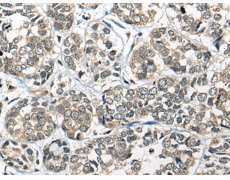

IHC positive control: |

Human liver cancer and human lung cancer |

IHC Recommend dilution: |

20-100 |